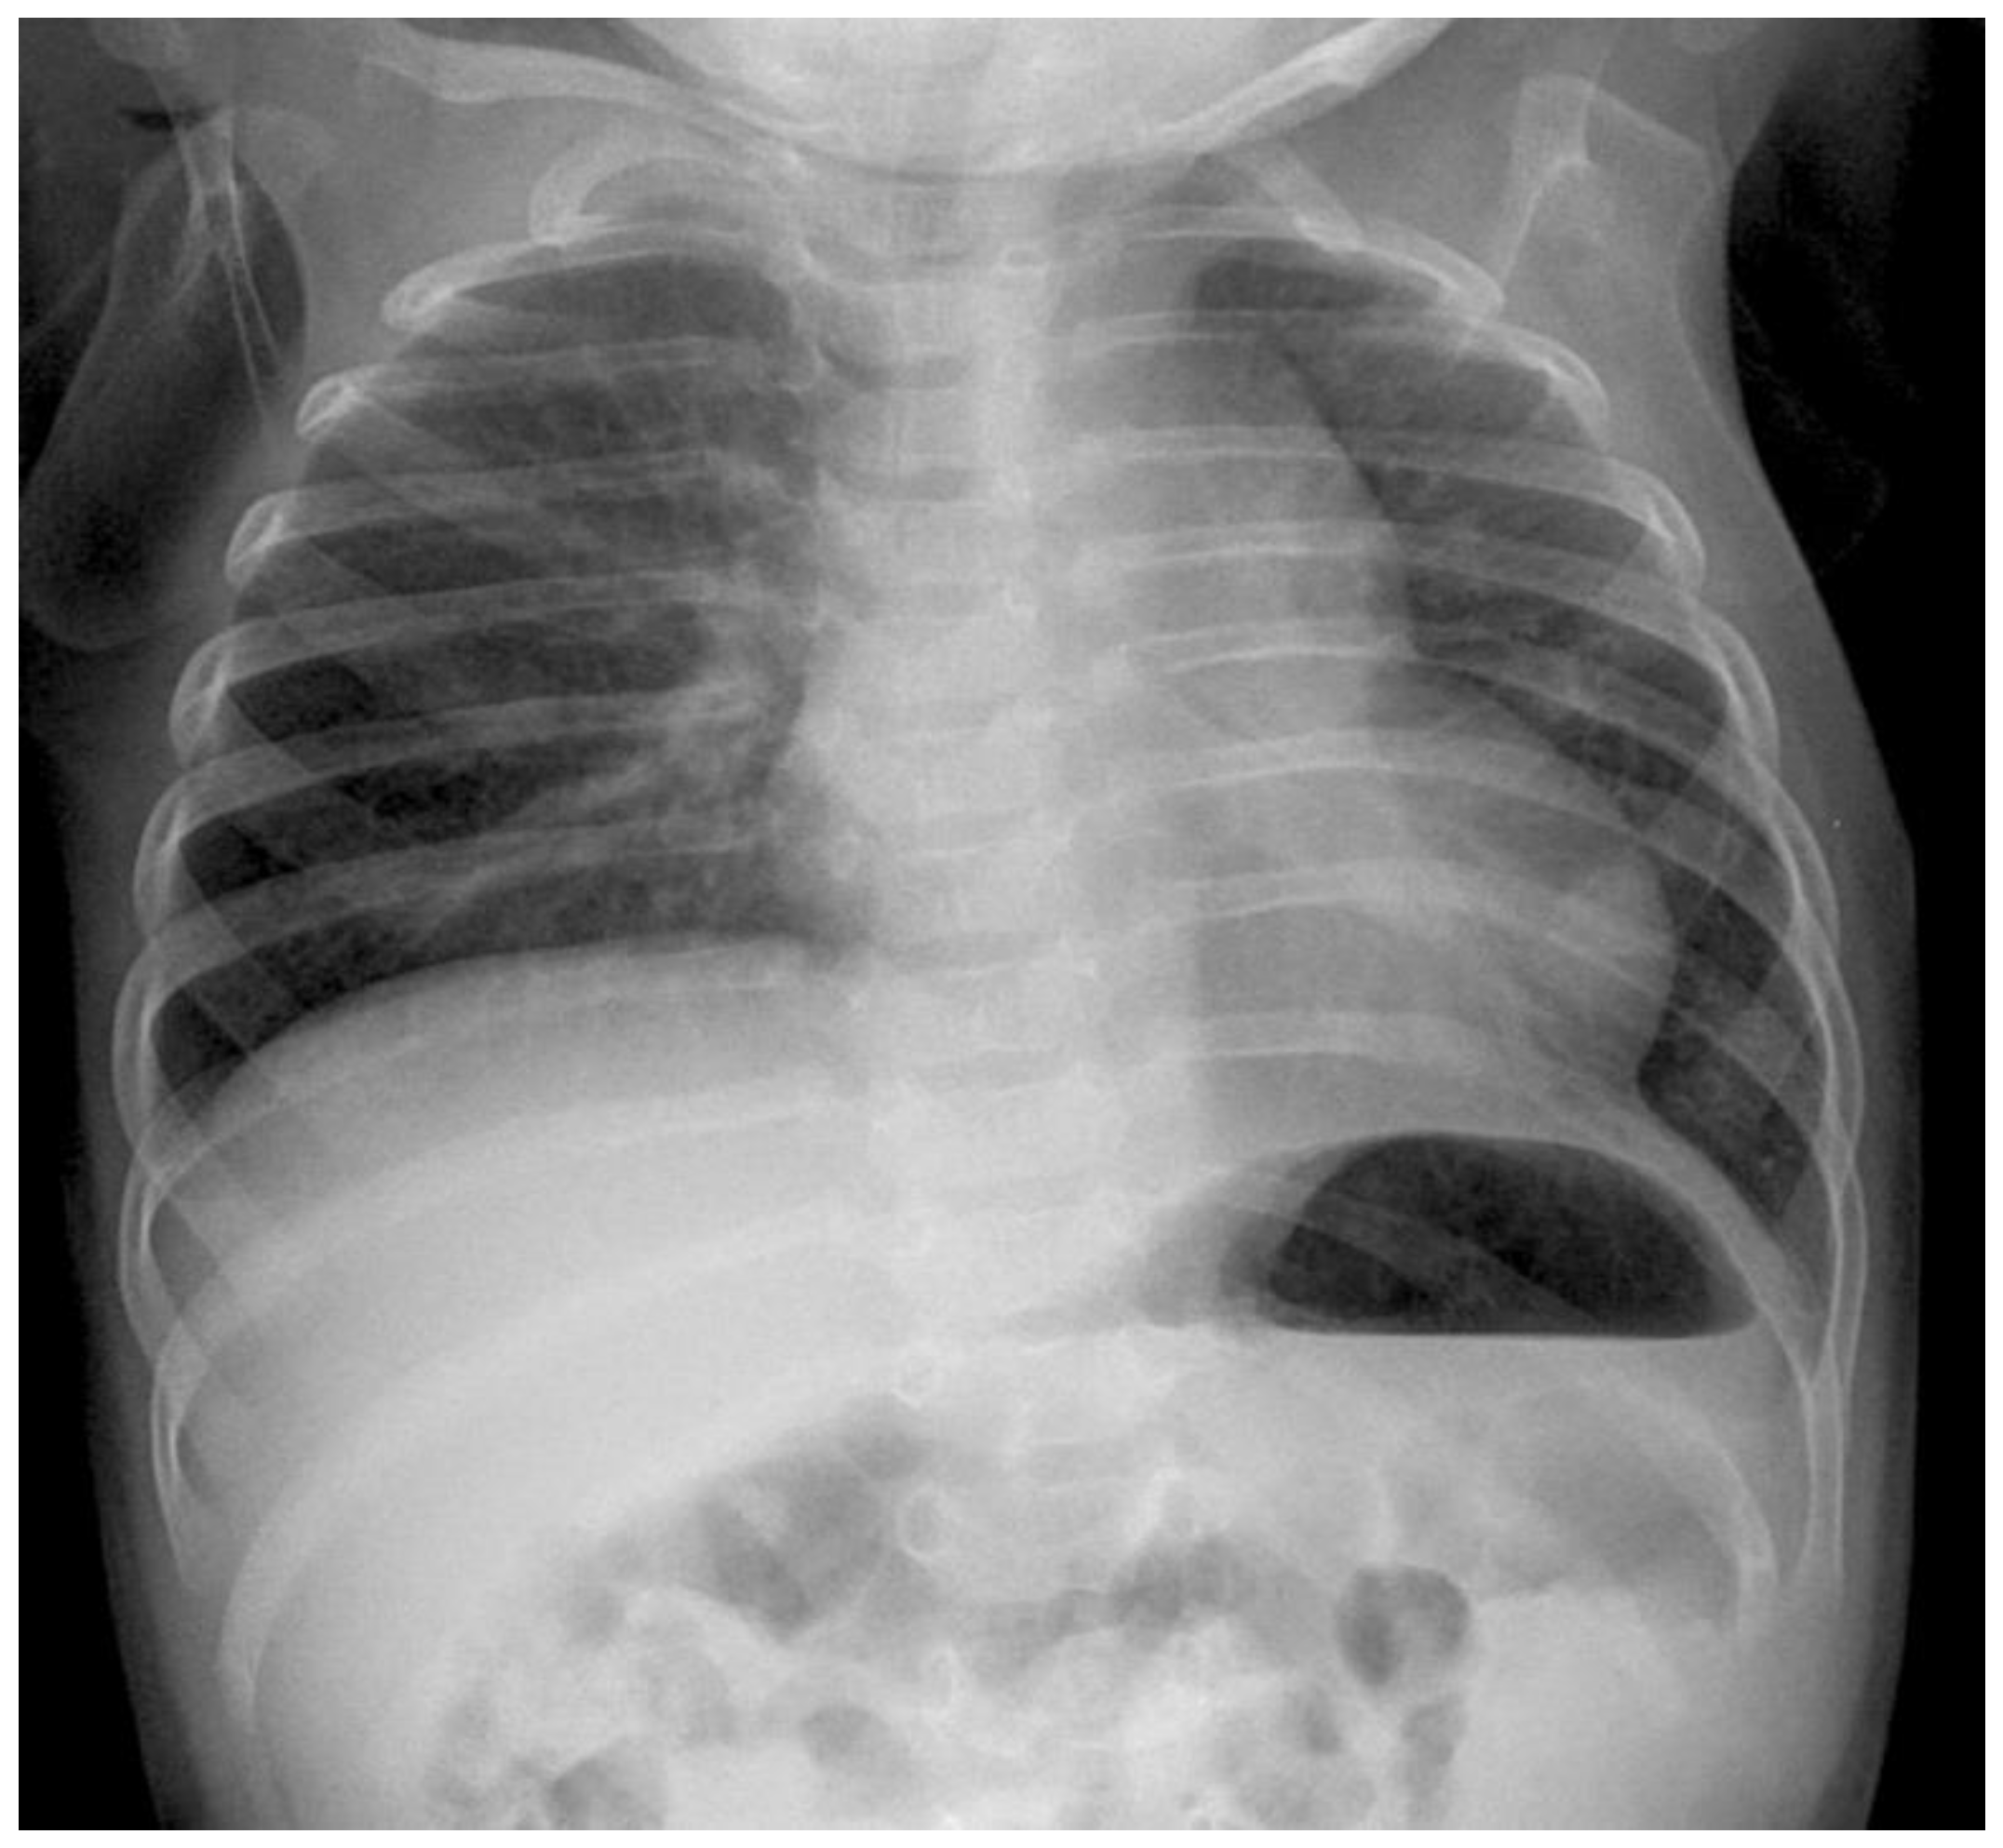

Preoperative Setting: After delivery, a plane X-ray image is taken at the intensive care unit (ICU) (see Figure 1). To rule out other associated anomalies, echocardiography and ultrasound of the brain and the abdominal organs are necessary. All patients were intubated between the first 2–4 h after birth in general to prevent abdominal distension and to avoid an additional compromise of the lung function. As soon as the patient is in a stable cardiorespiratory condition the surgical repair of the defect is performed. The patient is placed on the OR table in lateral decubitus position, the side of the defect upwards with an axillary roll underneath it, and the body is appropriately padded. The preoperative antiseptic routine is performed. Under complete relaxation by anesthesia three 3-mm trocars are placed in the standard location for CDH repair: one at the lower tip of the scapula for the camera, one in the frontal axillary line and one in the posterior. Insufflation pressures during operations are 3–6 mmHg with a flow of 1 L/min. Single lung ventilation is not needed. The herniated bowel is placed downwards into the abdomen and the size and nature of the defect are evaluated.

Figure 1. Preoperative radiograph of a left-sided CDH. The * indicates the intrathoracic bowel.